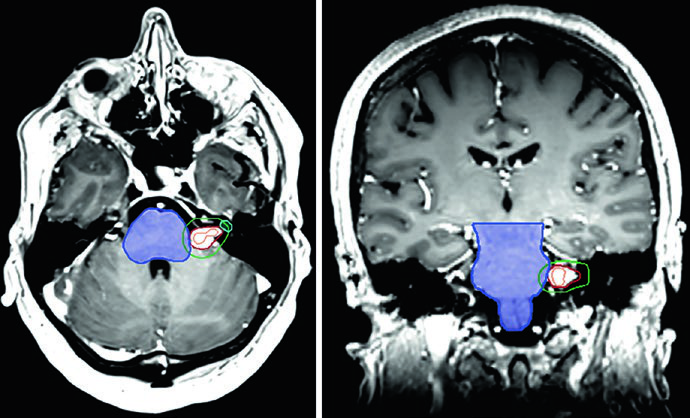

O caso da Figura 29.9 ilustra um schwannoma vestibular direito no ângulo cerebelopontino que comprime o pedúnculo cerebelar médio e a ponte, estendendo-se para o fundo do canal auditivo interno. Há compressão do tronco encefálico e do nervo trigêmeo cisternal, com apagamento parcial moderado do quarto ventrículo. Na Figura 29.10, o tratamento de um schwannoma do APC esquerdo com SRS a 12,5 Gy de prescrição mostra a isodose de prescrição cobrindo o tumor, com isodose de 20 Gy no centro e 5 Gy na periferia, preservando tronco encefálico e cóclea como OARs.